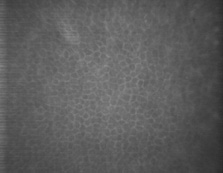

The human corneal endothelium is a single layer of 400,000 to 500,000 cells. Confocal microscopy provides views of this cell layer that surpass the details seen under specular microscopy (Figs. 19 and 20). Cells are 4 to 6 μm in height and 20 μm in width, and their posterior surfaces are predominantly hexagonal when viewed under specular microscopy (Fig. 21). Cross-sectional views with electron microscopy show that cell lateral walls are extremely tortuous and interdigitate with extensive folds and finger-like projections. It has been estimated that the total paracellular path length may be 10 times longer than the total height of the cell.90 Numerous gap junctions along the lateral membranes provide cell-to-cell cytoplasmic communication as evidenced by the presence of connexin 43 and the spreading of fluorescent dye from an injected cell to surrounding cells (Fig. 22).91

Fig. 19. Confocal microscopic transverse image of the human corneal endothelium in vivo. In the young normal cornea, the majority of the cells will have a hexagonal outline and they will be fairly uniform in size. The dark spots near the center in many of the cells may represent the central endothelial cilium (500×). (Courtesy of Nidek Technologies.)

Fig. 20. Confocal microscopic transverse image of the human corneal endothelium in vivo after penetrating keratoplasty. Note cellular enlargement, polymegathism, and polymorphism. Cell nuclei are clearly visible. Normally non-dividing, endothelial cells enlarge slowly with age to compensate for cell loss, maintaining a continuous lining on Descemet's membrane. Cataract surgery and transplants generally exhibit cell loss. Below about 400 cells per mm2 endothelial decompensation can occur with ensuing edema (500×). (Courtesy of Nidek Technologies.)

Fig. 21. Scanning electron micrograph of corneal endothelium. Note the regular hexagonal arrangement of the cells (1,170×). (Courtesy of Drs. Rodrigues, Waring, Hackett, and Donohoo.)

Fig. 22. Scanning electron micrograph of endothelial cell intracellular junctions (8,100×). (Courtesy of Drs. Rodrigues, Waring, Hackett, and Donohoo.)

The apical portion of the lateral cell membranes facing the anterior chamber possesses small flap-like or leaflet-like features that overlap adjacent cells and harbor segmented tight junctions that form an incomplete seal around the apical cell margin (Fig. 23). Megamolecules (greater than 80 kd) are essentially prevented from penetrating the paracellular pathway, but molecules such as horseradish peroxidase and lanthanum are able to cross the apical junctions.92,93 While these tight junctions appear dimensionally larger than those found in the apical cells of the epithelium, they are not as efficient.90 Nevertheless, these junctions, combined with the closely apposed paracellular pathway, prevent excessive passive transport of anterior chamber fluid into the stroma. Any normal leakage that may occur around the endothelial cells tends to be counterbalanced by the active ion transport processes in the cell membranes. With pathologic cellular damage or substantial reduction in cell density from a normal value between 1,400 and 2,500 cells/mm2 to a critical value of approximately 400 to 700 cells/mm2, the endothelial transport capability becomes overwhelmed, and chronic stromal edema can ensue.90 Endothelial cell density normally increases from the center to peripheral cornea by approximately 10%, with the superior peripheral quadrant increasing by nearly 16%.94

The normal central corneal endothelium has been shown to have a reduction in the cell density over a 10-year period. Repeated specular microscopy in the same individuals over a 10-year period with the same camera and processing method indicates that cell density decreased from a mean of 2,715 ± 301 to 2,539 ± 284 cells per square millimeter (p < 0.0001). The percentage of hexagonal cells dropped over the same time period from 67% to 64% (p = 0.003), while the coefficient of variation increased from 0.26 ± 0.05 to 0.29 ± 0.06 (p < 0.001).95